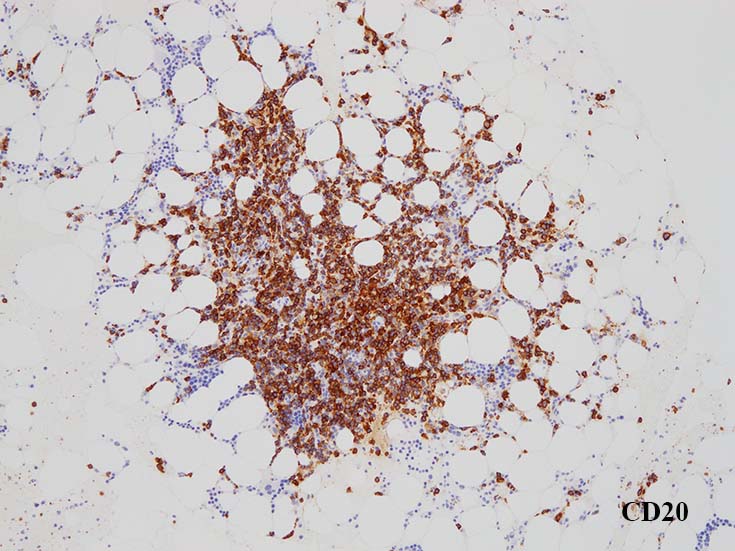

Bone marrow clot sectionでは, nodularな病変形成が認められる. HEでは不明瞭であるが, Naphtol-ASD-CAE-Giemas染色では mast cellの顕著な増加が明瞭に認識される.

増殖するB細胞はCD19+, CD20+. 結節内に増加する形質細胞はCD19+, CD20‐である. (多発性骨髄腫の形質細胞様細胞はCD19陰性).~  多くのB細胞がMUM1陽性を示す. CD5, CD10, BCL6は陰性.